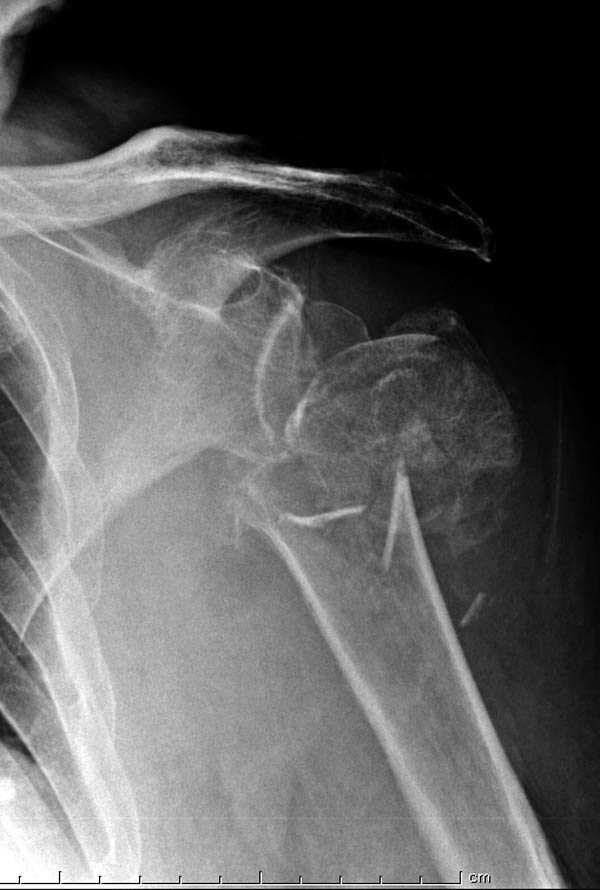

дополнительные снимки по протезированию

Имя     : Shoulder 3.jpg

Тип     : image/jpeg

Размер  : 42444 байтов

Url     : http://weborto.net:8080/pipermail/ortho/attachments/20090420/0ada04e1/attachment-0005.jpg